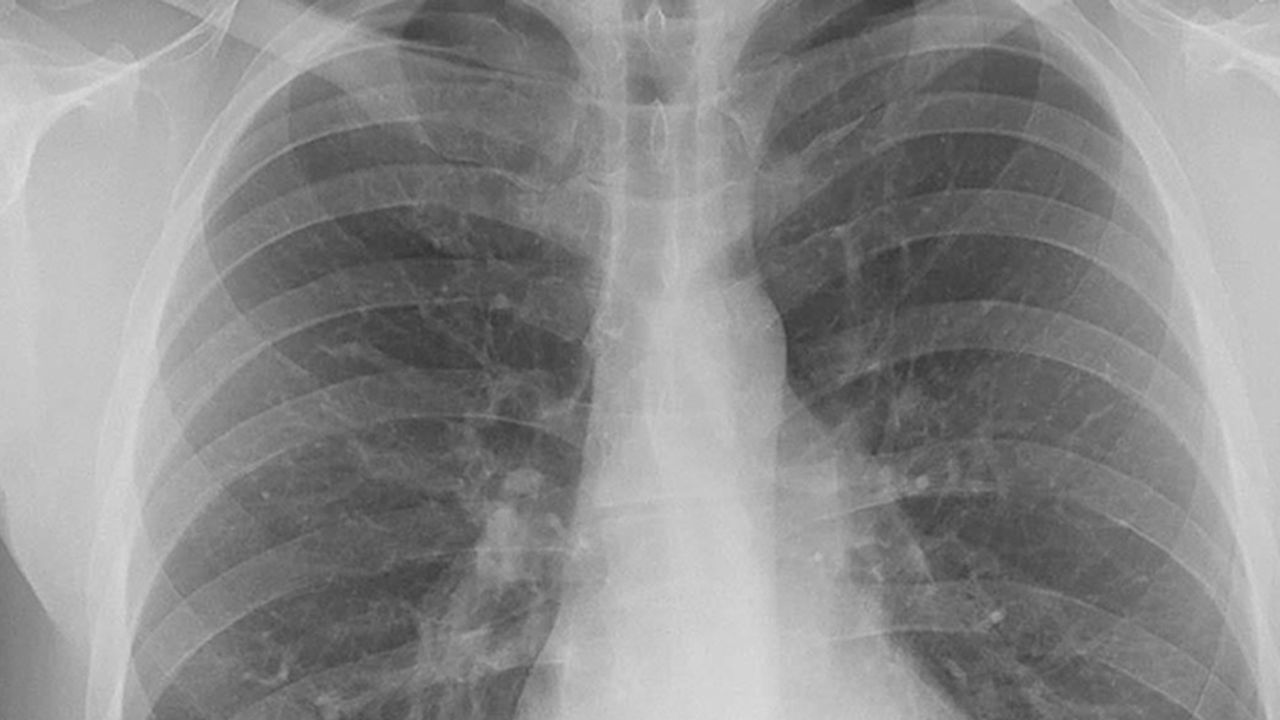

Belirtiler genellikle hafif başladığını vurgulayan Yazıcı, "Geçmeyen öksürükler, balgamda kan görülmesi, nefes darlığı, sırt ağrıları, göğüs ağrıları, açıklanamayan kilo kayıpları olabilir. Şikâyetleri mevsimsel veya sigara kaynaklı deyip, geçiştirmemek gereklidir. Çünkü bu belirtiler hastalığın erken evre habercileri olabilir. Günümüzde tıbbın ilerlemesi ile birlikte tanı için çeşitli görüntüleme yöntemlerimiz var. Şüphe dahilinde ve hastanın akciğer grafisinde uyumlu belirtiler varlığında hastalarımıza tomografi kontrolleri yapmaktayız. Bu kontroller sayesinde hastalarımız daha erken tanı alabilmektedir. Bu da tedavi başarısını ve hastaların yaşam süresini ciddi şekilde arttırmaktadır" dedi.